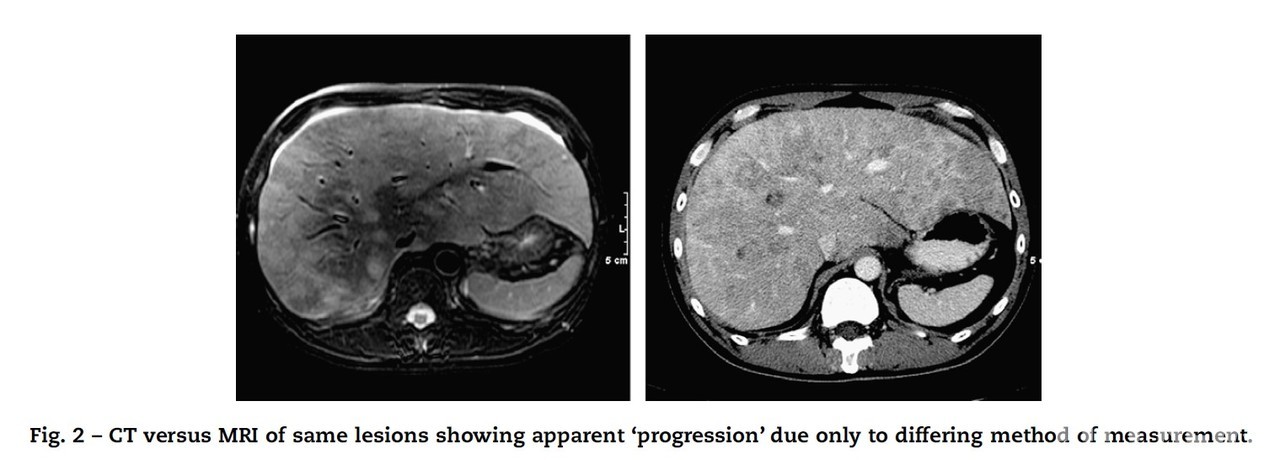

일반적으로 임상시험의 각 유효성 평가변수들은 연구자들에 의해 평가되기 때문에 주요 변수로 독립적 영상 평가를 도입하기 위해서는 추가 절차가 필요하다. 독립적 영상 평가는 치료계획 등과 같은 임상시험 정보를 눈가림으로 디자인한 항암신약 분야 임상에서 수요가 많다. 보통 CT나 MRI 영상을 가지고 종양의 크기를 측정하게 하고, 종양의 크기를 측정할 때 단순 크기를 측정하는 것이 아닌 명확한 기준에 따라 평가가 진행된다.